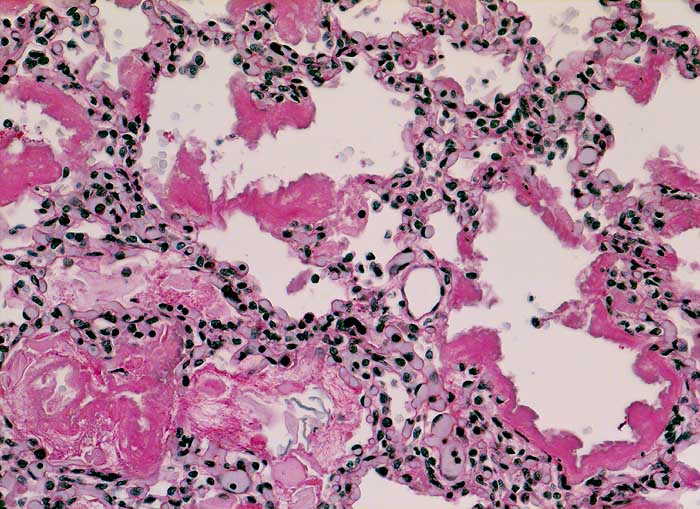

AP/ Hyaline-Membranen-Krankheit des Neugeborenen

Hyaline-Membranen-Krankheit des Neugeborenen

Lunge, Mediastinum mit Thymus

Lunge